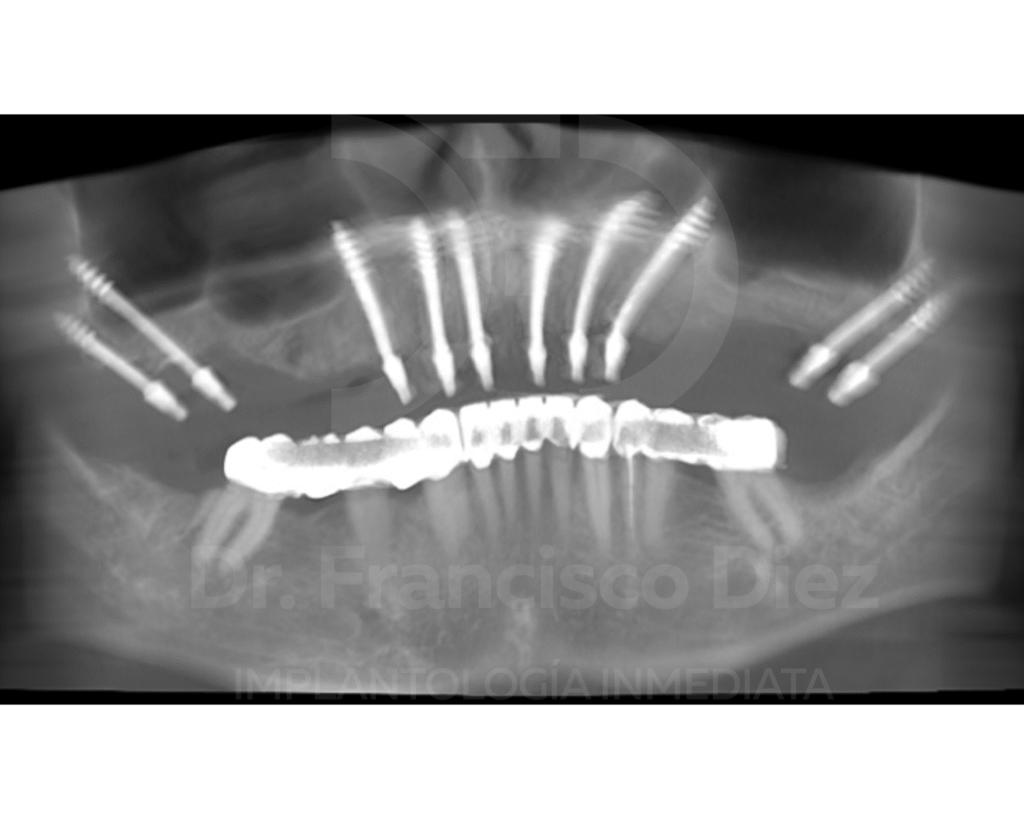

El estudio radiológico mediante tomografía computarizada reveló además implantes convencionales afectados con periimplantitis y un déficit óseo importante en las zonas posteriores del maxilar superior, lo que hacía inviable una rehabilitación mediante implantología convencional sin recurrir a injertos óseos y largos tiempos de espera.

En una única intervención se procedió a la extracción de todos los dientes del maxilar superior y a la colocación inmediata de 10 implantes córticobasales BCS, anclados en hueso cortical. Esta técnica permite tratar casos con atrofia ósea severa sin necesidad de injertos, reduciendo de forma significativa la invasividad del tratamiento.